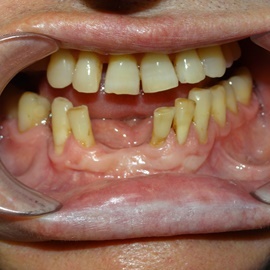

Pacjentka lat 58, prowadzi aktywne życie zawodowe. Odczuwała dyskomfort przy użytkowaniu protezy, dodatkowo przy uśmiechu odsłaniała klamry utrzymujące protezę.